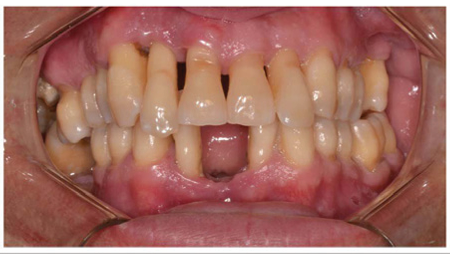

A 36-year-old male patient, melanoderma, was referred to the Specialization Course in Periodontics at the UFRGS Dental Clinic, complaining of marked mobility in all teeth of the mouth (Figure 1 and 2).

Figure 1 Initial photo - Front view.